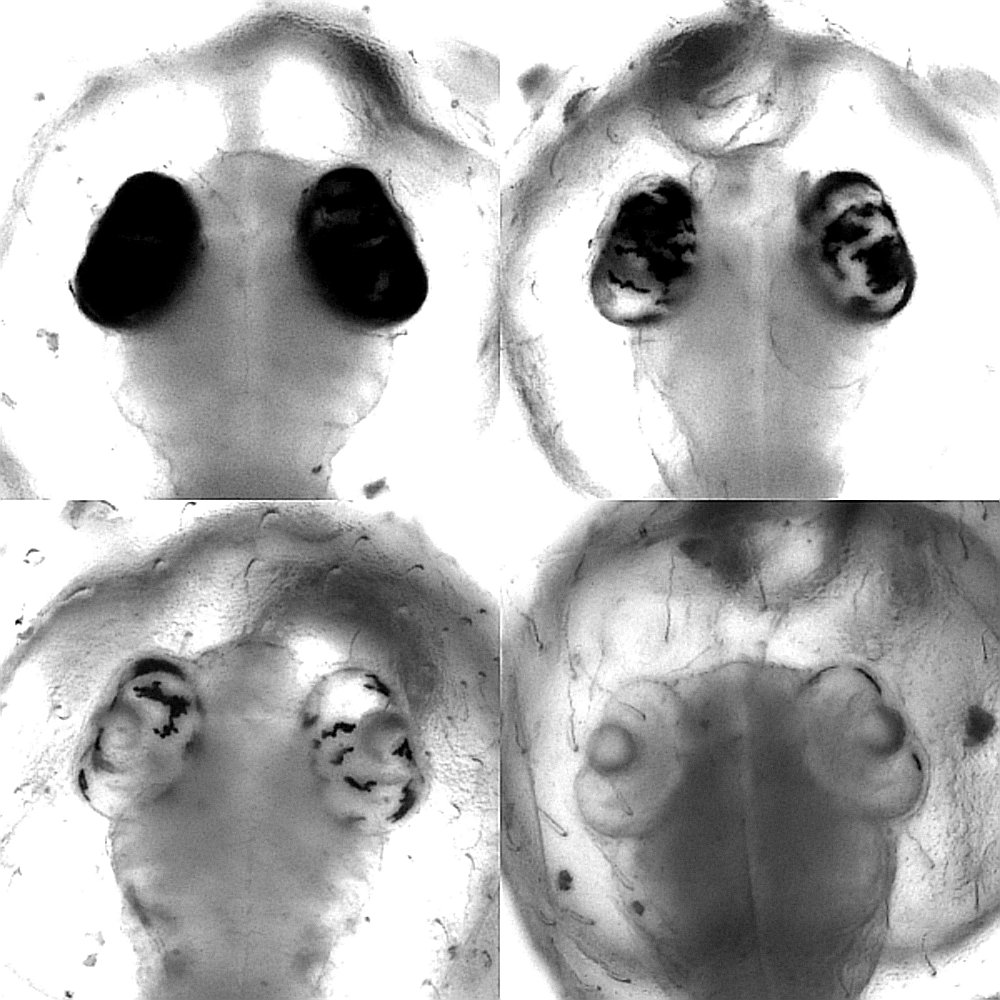

In a further study, the Heidelberg scientists showed that base editors operate highly efficiently in the living organism and are even suited to genetic screening. In an experiment with Japanese rice fish, they were able to show that these locally limited, targeted modifications in individual buildings blocks of the DNA achieve an outcome that is otherwise only obtained by the comparatively laborious breeding of organisms with altered genes. The research team at COS, in cooperation with Dr Dr Jakob Gierten, a paediatric cardiologist at Heidelberg University Hospital, focused on certain genetic mutations. These mutations were suspected of triggering congenital heart defects in humans. Through modifying individual building blocks of the DNA of the relevant genes in the model organism, the scientists were able to imitate and study fish embryos with the described heart defects. The targeted intervention led to visible changes in the heart already during early stages of fish embryonic development, say Bettina Welz and Dr Alex Cornean, two of the first authors of the study from Prof. Wittbrodt’s team. That enabled the researchers to confirm the original suspicion and establish a causal connection between genetic alteration and clinical symptoms.

The precise intervention in the genome of the fish embryos was made possible through especially developed software ACEofBASEs, which is available online. It allows for identifying genetic locations that very efficiently lead to desired changes in the target genes and the resultant proteins. The scientists say that the Japanese ricefish is an excellent genetic model organism for modelling mutations like those identified from the respective patients. “Our method enables an efficient screening analysis and could therefore offer a starting point for developing individualised medical treatment,” according to Jakob Gierten.